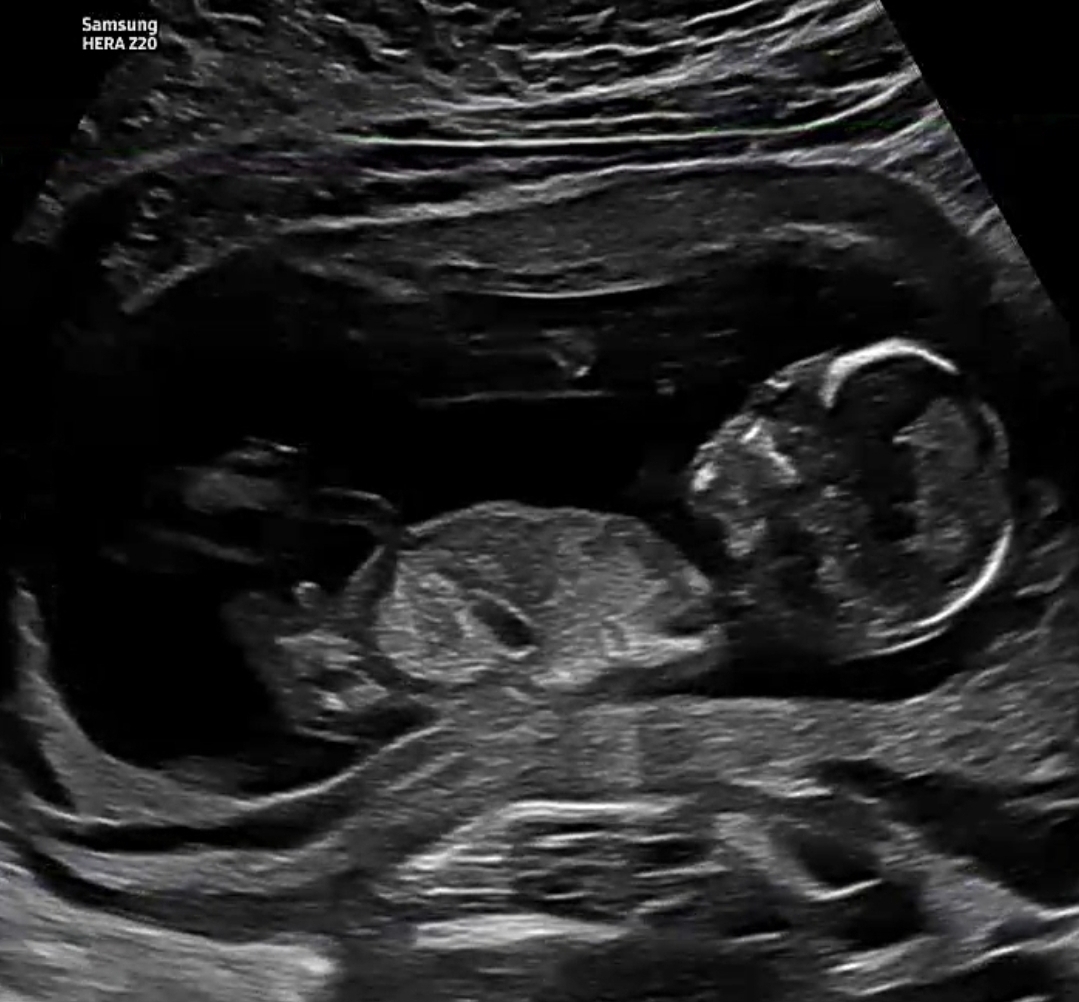

13주 0일 각도법 고수님들 부탁드려요!!

13주 0일에 초음파 찍었어요! 저게 생식기인지도 구별이 안가는데... 고수님들 투표 한번 부탁드립니다 ㅠㅠ 빌리는 딸이라는데 도대체가 넘 궁금하네요,,,,,,,그냥 니프티 할걸 각도법 지옥에 빠져있어요.....